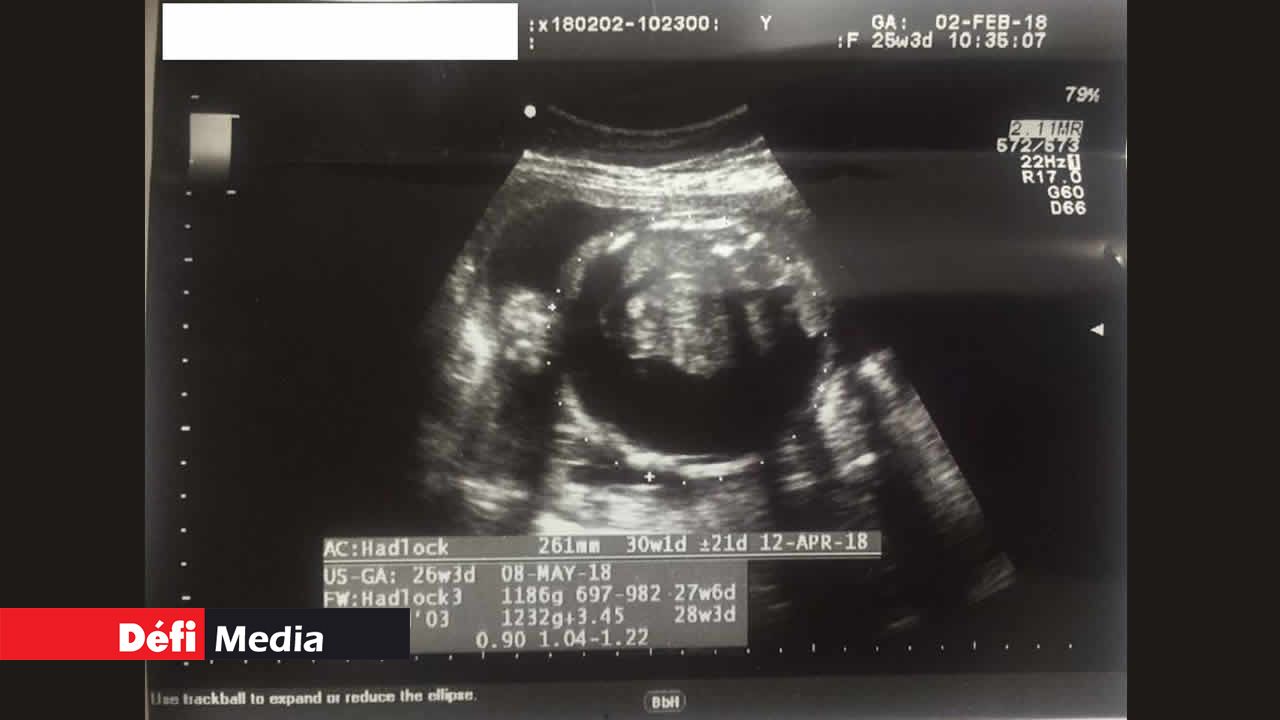

Le 22 décembre 2017, la femme en est à son quatrième mois de grossesse. Des boutons ‘anormaux’ sont apparus sur son ventre et elle ne se sent pas bien. Elle effectue sa première échographie et son médecin traitant à l’hôpital lui confirme que tout va bien pour le bébé et pour elle-même. Quelques jours après, vu qu’elle n’était toujours pas rassurée, elle décide de solliciter l’avis d’un autre gynécologue du privé. Après examen, la mauvaise nouvelle tombe : il y a de l’eau dans le ventre de son bébé.

Le médecin privé réfère Padmini à un confrère radiologue (toujours du privé) pour avoir un deuxième avis. « Effectivement, selon les résultats du deuxième examen, l’eau avait atteint 10 mm dans le ventre de mon bébé. Le gynécologue du privé m’a déclaré que la situation risquait d’empirer, puisque le volume d’eau pouvait augmenter et que c’est dangereux pour le bébé. Et d’ajouter que, normalement, à 16 semaines de grossesse, cette situation est visible lors de l’échographie », explique Padmini.